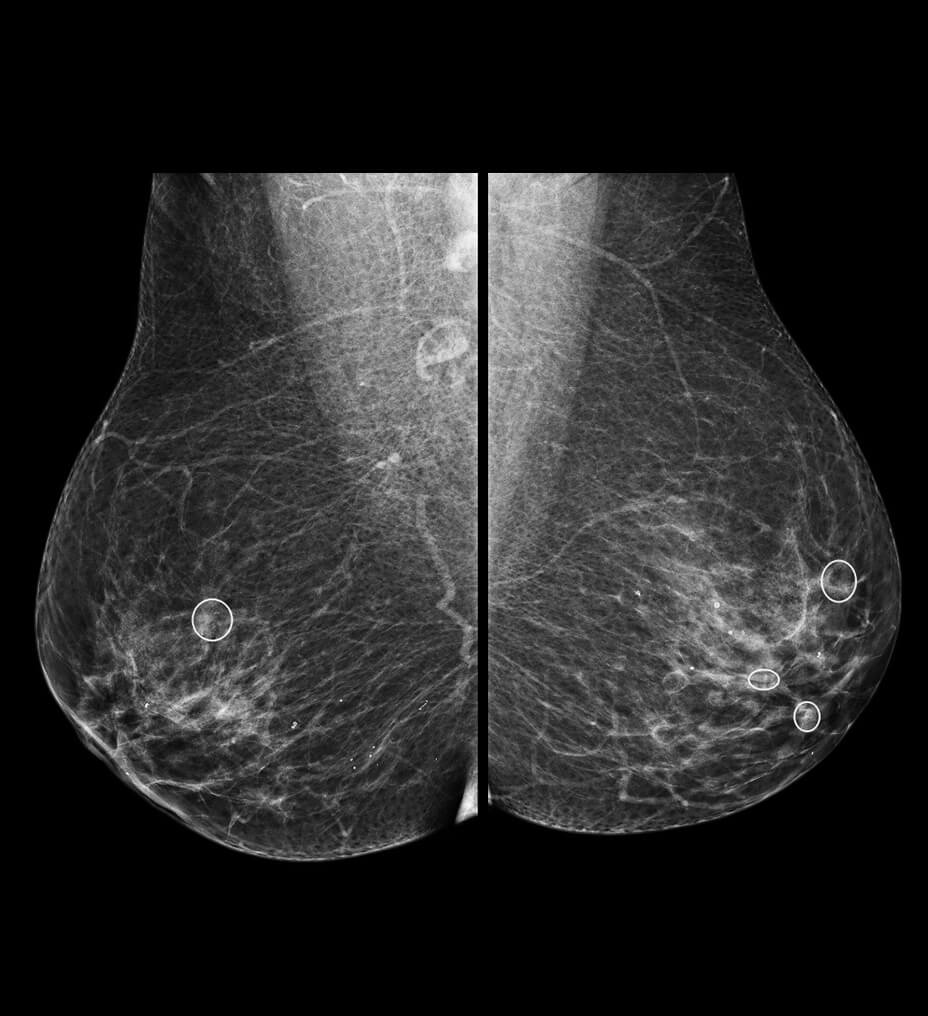

• Quantitation

Accurate data points to trusted treatment

With Discovery IQ Gen 2, your quantitation is no longer limited by the technologies used to produce it. Compared to conventional methods, Discovery IQ Gen 2 uses more accurate and consistent quantitative tools like Q.Clear to support your treatment with precise data points. This allows your SUV measurement to become more than a number. It becomes a tool for trusted clinical discovery, diagnosis and treatment assessment.

• Up to a 2x improvement in image quality (SNR)

• Up to a 2x improvement in quantitative SUV (SUVmean)